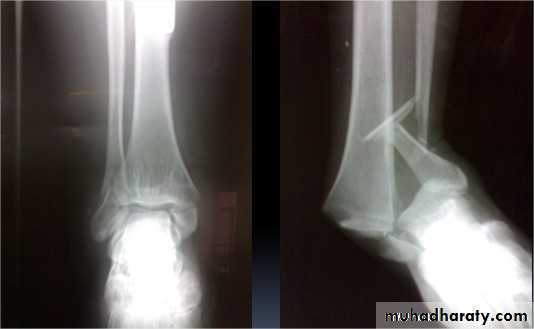

Comminuted fractures of the tibial plafond (Pilon fracture)

Severe axial compression of the ankle (FFH).

Shattering of ankle joint surface.

Swelling and blistering; treated by elevation and calcaneal traction.

Secondary Osteoarthritis is common.